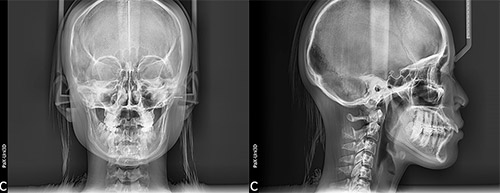

精密検査

顔の骨格を調べられる矯正治療用のレントゲン写真撮影装置「セファログラム」(頭部X線規格写真撮影装置)を使い、顎の大きさやズレ、歯の傾斜、口元のバランスなどを把握します。